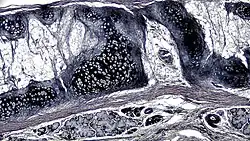

| .jpg.webp) A cross section of mammalian elastic cartilage | |

|  Lateral side of the auricle | |

Elastic cartilage, fibroelastic cartilage or yellow fibrocartilage [1] is a type of cartilage present in the pinnae (auricles) of the ear giving it shape,[2] provides shape for the lateral region of the external auditory meatus,[3] medial part of the auditory canal[3] Eustachian tube, corniculate and cuneiform laryneal cartilages,[3] and the epiglottis. It contains elastic fiber networks and collagen type II fibers.[4] The principal protein is elastin.

Elastic cartilage is histologically similar to hyaline cartilage but contains many yellow elastic fibers lying in a solid matrix. These fibers form bundles that appear dark under a microscope. The elastic fibers require special staining since when it is stained using haematoxylin and eosin (H&E) stain it appears the same as hyaline cartilage.[3] Verhoeff van Geison stains are used (giving the elastic fibers a black color), but aldehyde fuchsin stains, Weigert's elastic stains, and orcein stains also work.[3] These fibers give elastic cartilage great flexibility so that it is able to withstand repeated bending. Similarly to hyaline one or multiple chondrocytes lie between the spaces (or lacunea) in the fibres.[2] The chondrocytes only make up 2% of the tissue's volume.[2] Chondrocytes and the extracellular matrix are contained in an outerlayer named the perichondrium[2] (which is a layer of dense irregular connective tissue that surrounds cartilage which is independent of the joint).[3] It is found in the epiglottis (part of the larynx), and the pinnae (the external ear flaps of many mammals). Elastin fibers stain dark purple/black with Verhoeff's stain.